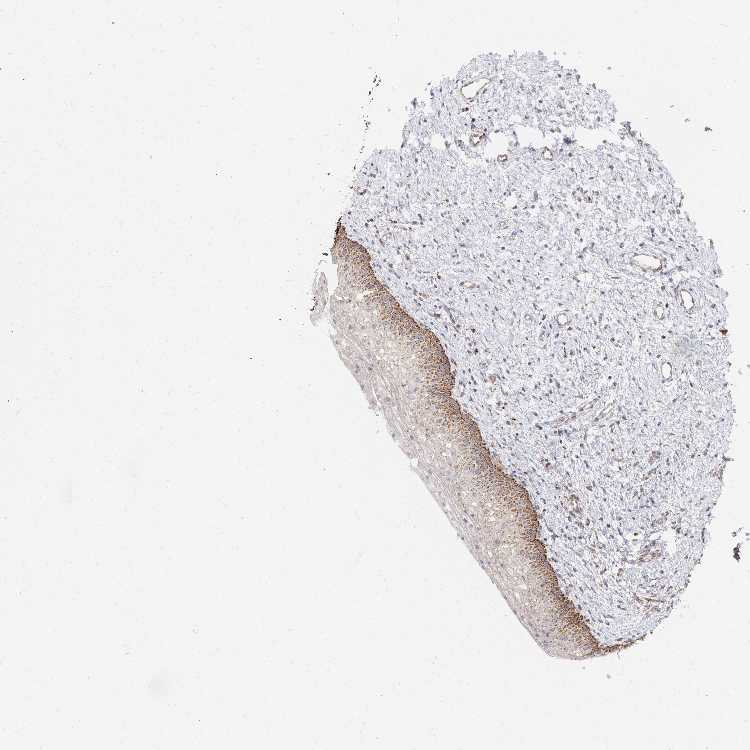

VAGINA - Antibody stainingi

Antibody staining in the annotated cell types in the current human tissue is reported as not detected, low, medium, or high, based on conventional immunohistochemistry profiling in selected tissues. This score is based on the combination of the staining intensity and fraction of stained cells.

Each image is clickable and will lead to virtual microscopy that enables deeper exploration of all samples and also displays staining intensity scores, fraction scores and subcellular localization as well as patient and tissue information for each sample.

Antibody HPA062016

Squamous epithelial cells High